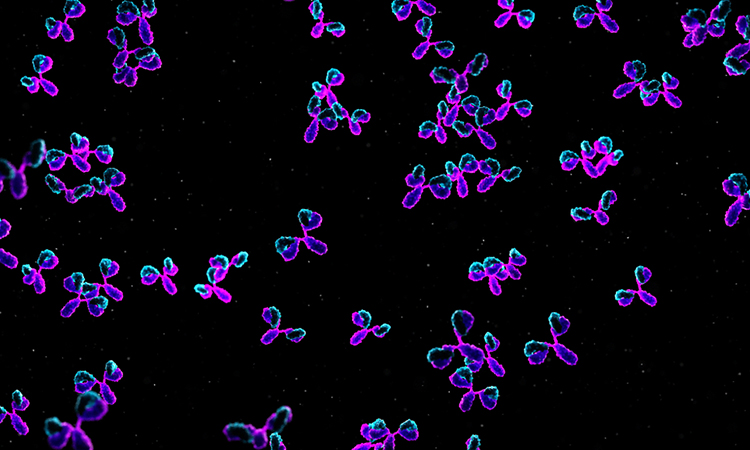

B cell discovery could supercharge future vaccine development

New research reveals how B cells balance mutation and clonal expansion to refine their antibodies. This discovery could lead to more targeted and effective vaccine designs for various diseases.